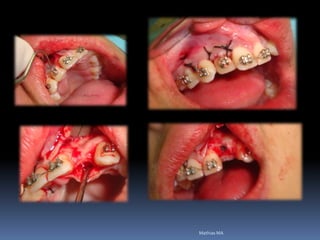

Atrofias ósseas

•Procedimentos de enxertia óssea para

restabelecimento de dimensões perdidas

•Compensações dos tecidos perdidos nas

próteses